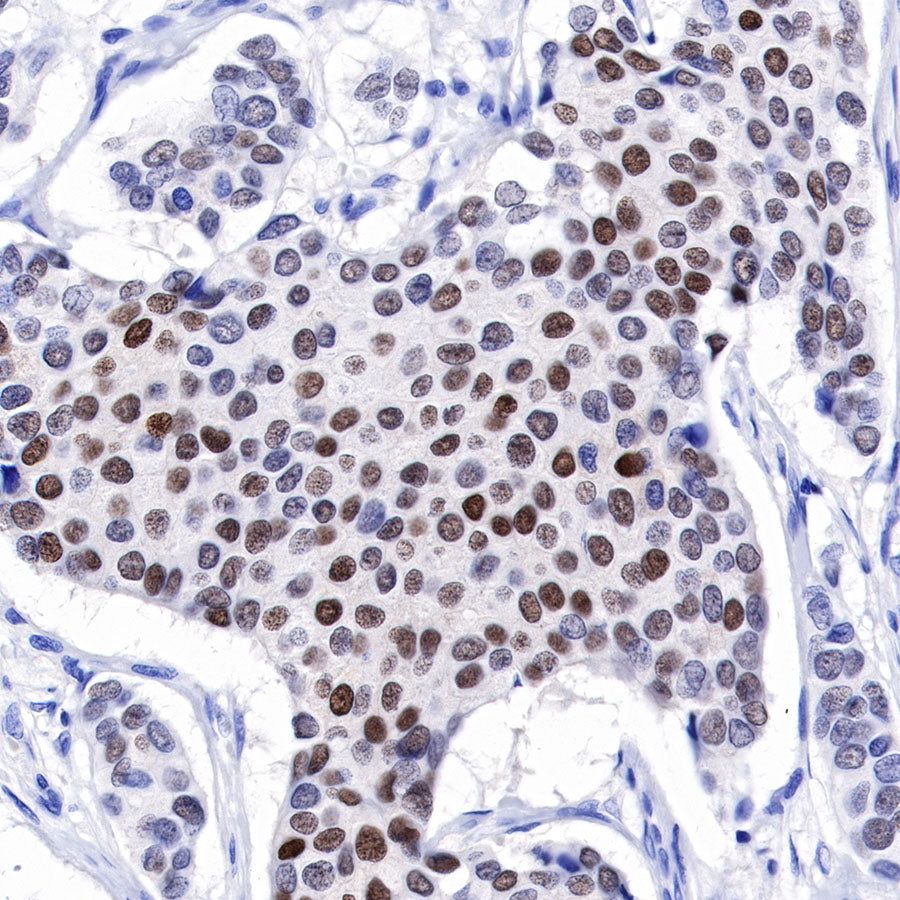

IHC shows positive staining in paraffin-embedded human breast. Anti-Progesterone Receptor antibody was used at 1/500 dilution, followed by a HRP Polymer for Mouse & Rabbit IgG (ready to use). Counterstained with hematoxylin. Heat mediated antigen retrieval with Tris/EDTA buffer pH9.0 was performed before commencing with IHC staining protocol.

IHC shows positive staining in paraffin-embedded human breast cancer. Anti-Progesterone Receptor antibody was used at 1/500 dilution, followed by a HRP Polymer for Mouse & Rabbit IgG (ready to use). Counterstained with hematoxylin. Heat mediated antigen retrieval with Tris/EDTA buffer pH9.0 was performed before commencing with IHC staining protocol.